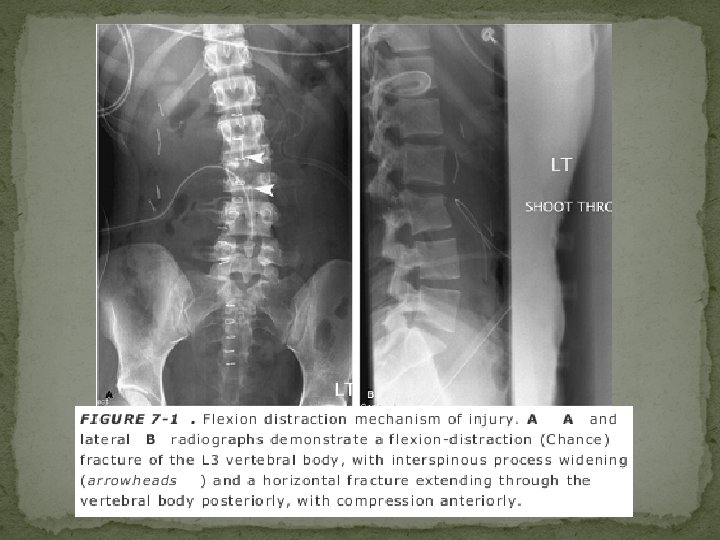

Flexion/Distraction Injury �most common at the thoracolumbar junction �separation in a cranial-caudal direction. �Resultant fracture is called Chance’s frcature. �Mechanism - result of hyperflexion of the upper thoracic spine while the lower spine remains relatively fixed �classically caused by a deceleration-type motor vehicle accident

“Classic Chance fracture” : �The classic Chance fracture accounts for approximately 50% of Chance-type injuries �A “classic” Chance fracture - consists of a pure osseous injury in which there is a horizontal split through the spinous process, lamina, pedicles, resulting in a small anteroinferior corner fracture of the lower vertebral body �acutely unstable �purely an osseous disruption; it also has excellent healing potential with good prognosis for long-term stability �Incidence of neurologic deficit is low, estimated at 10%

�AP radiographs - “double” spinous process, interspinous distance widening, and horizontal fractures through the pedicles �lateral radiograph is often unreliable due to overlap Chance variants – �are either a combined osseous/soft tissue injury or pure �The fracture may extend through the posterior elements as for the classic Chance fracture, but continues anteriorly through the disc or it may involve the posterior ligaments and vertebral body. soft tissue disruption.